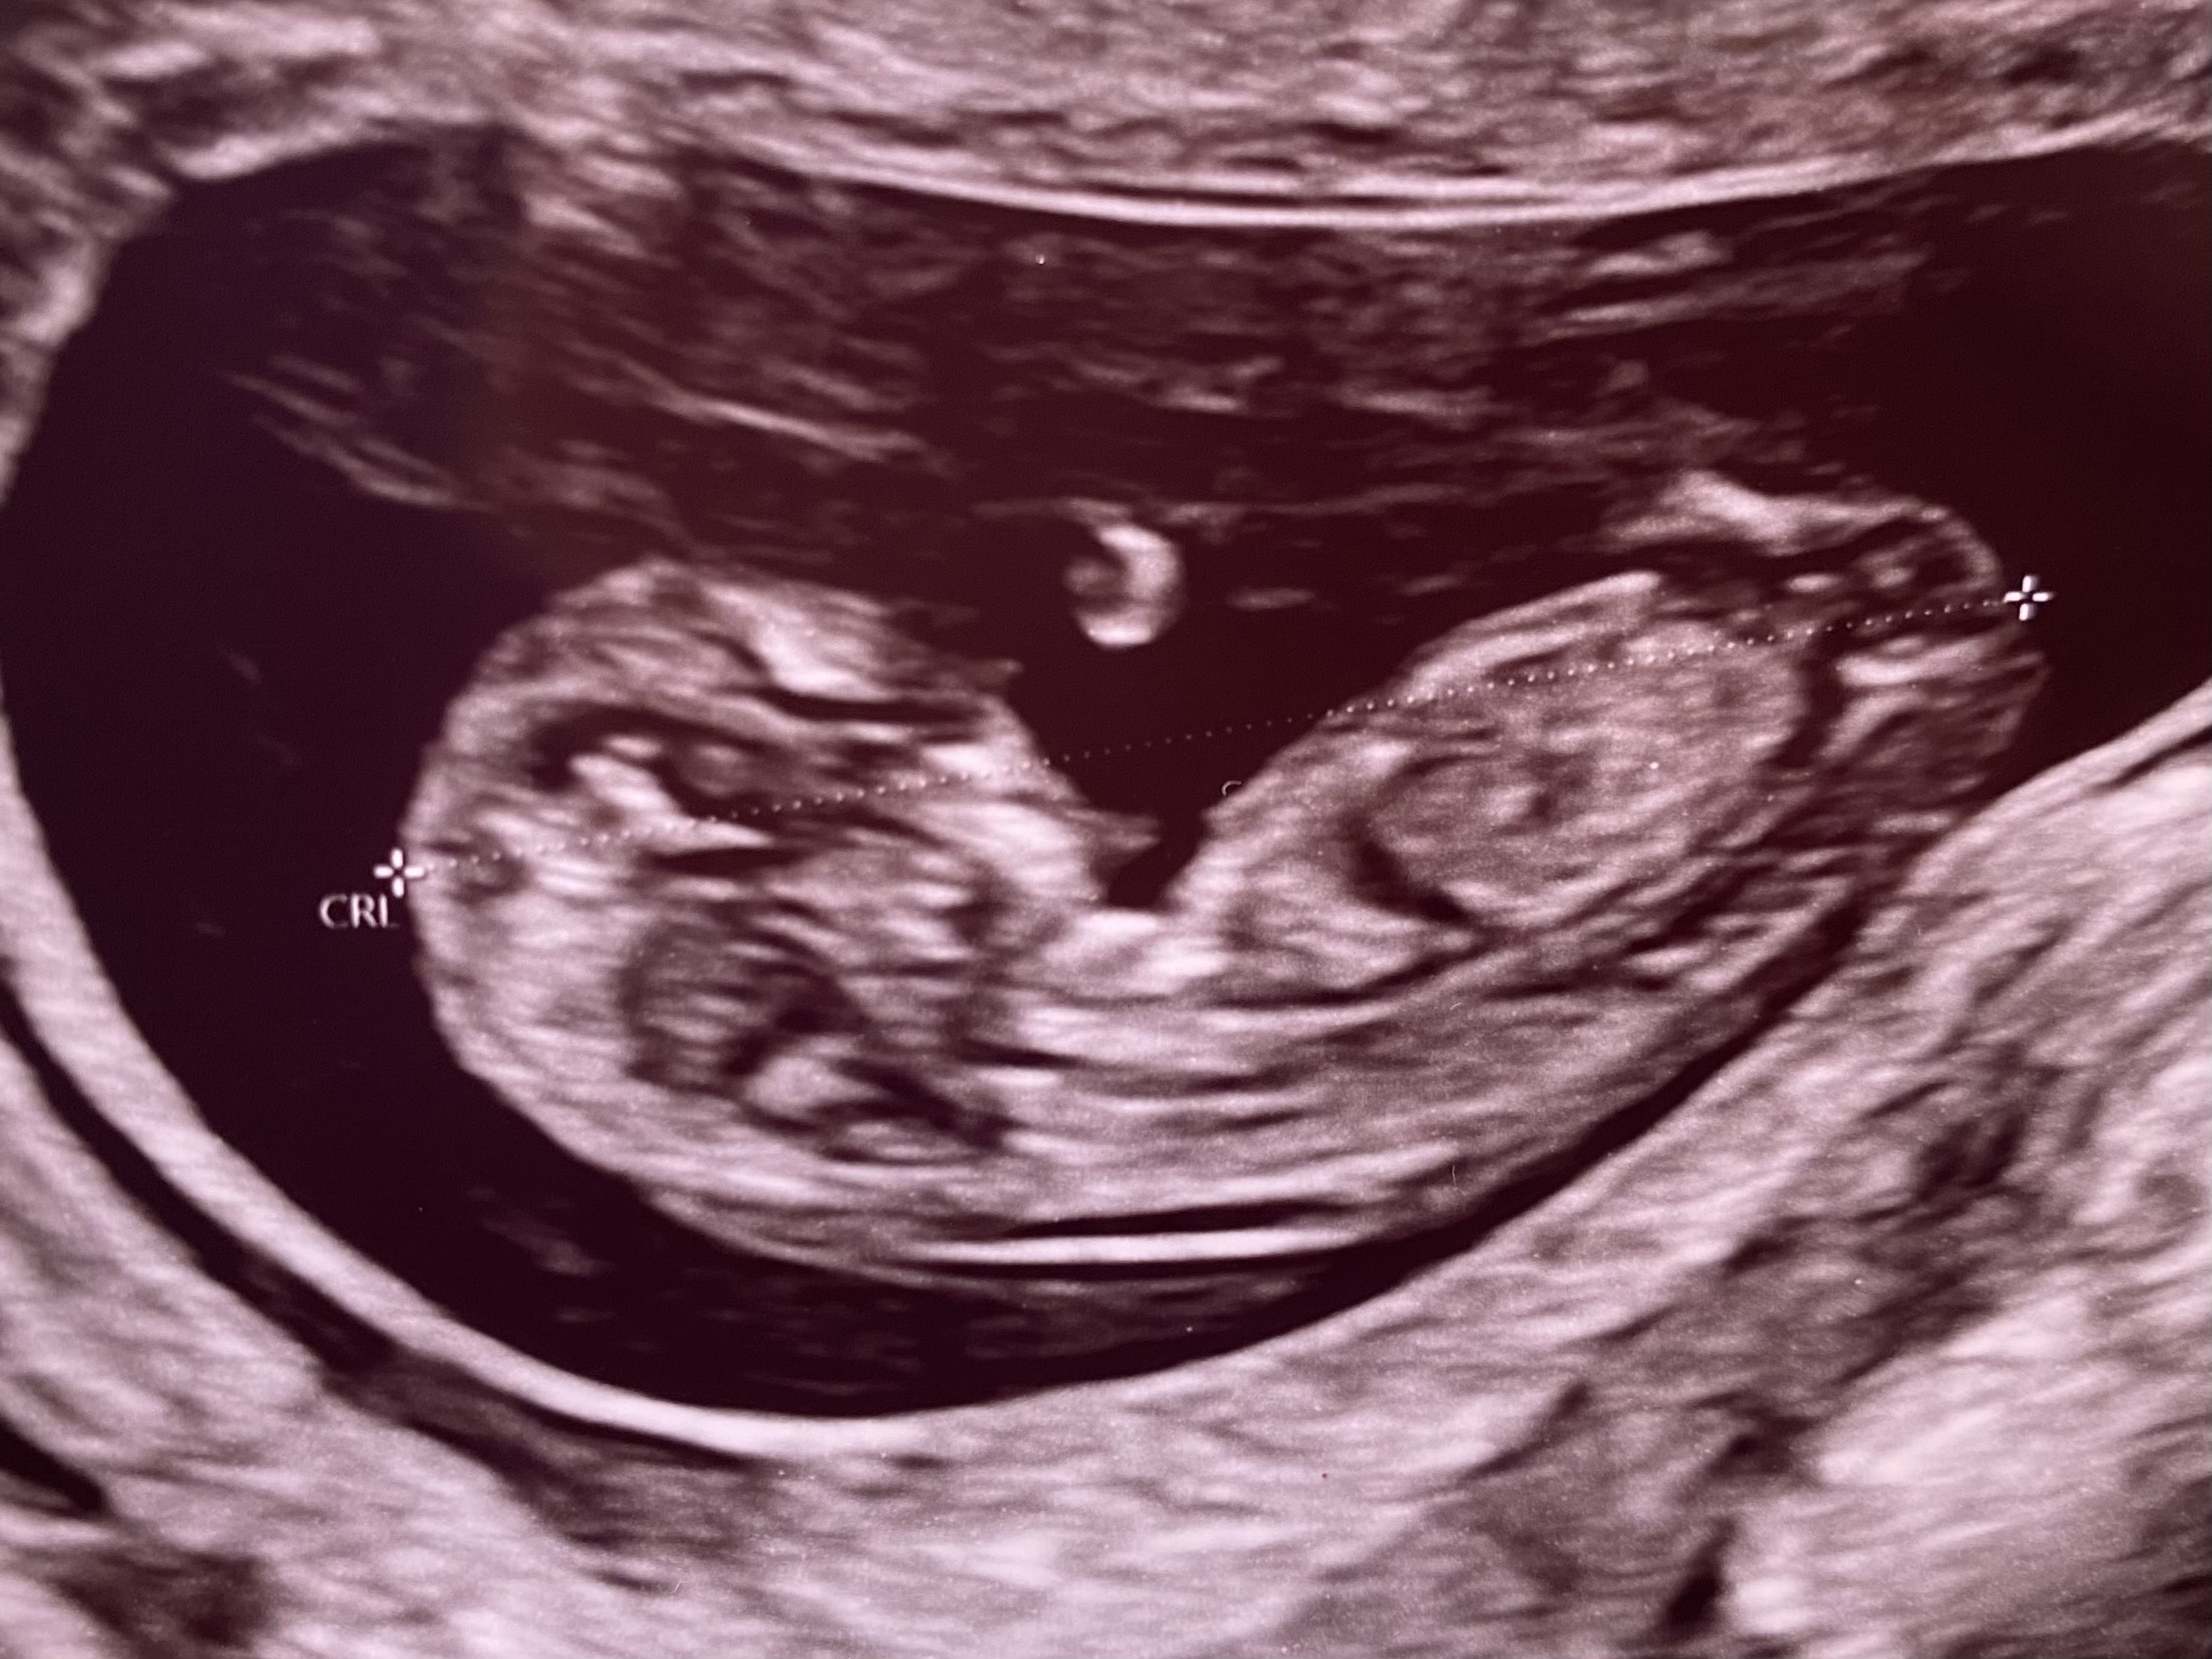

(투표) 둘째 성별 각도법 봐주세요!

잘 보시는 분들 투표 함 해주세요🥹